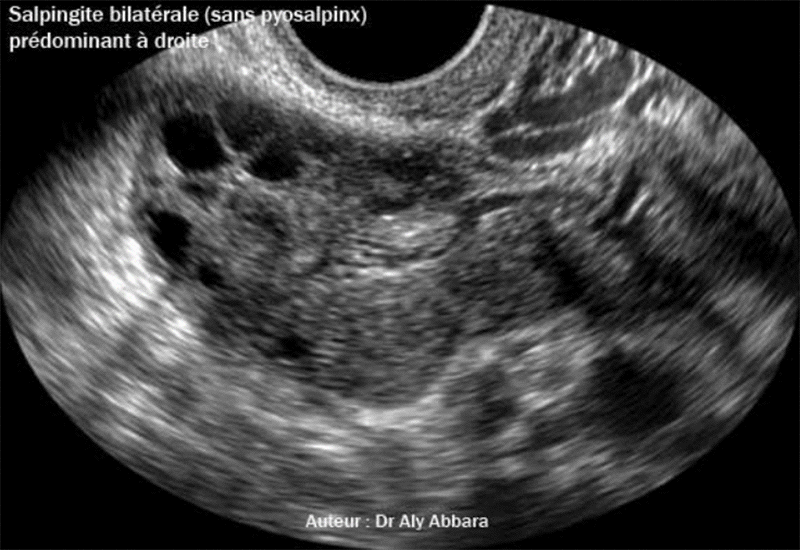

Image animée montrant un des aspects échographiques des trompes atteintes de salpingite aiguë bilatérale prédominant à droite et sans la formation d'abcès intra-tubaire (sans pyosalpinx).

Le diagnostic de salpingite aiguë a été confirmé suite à la réalisation d'une cœlioscopie exploratrice permettant la mise en évidence de la présence d'une trompe droite congestive, indurée, inflammatoire, triplée de diamètre et recouverte par de fausses membranes de formation récemment formées, puis une faible quantité d'épanchement péri-annexiel droit formé du pus. La trompe gauche présente les mêmes altérations constatées au niveau de la trompe droite, mais avec une moindre intensité.

A comparer avec une salpingite et pyosalpinx bilatéral.